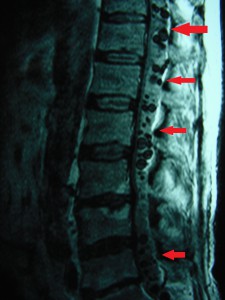

DSC00060_bakas_echinococos